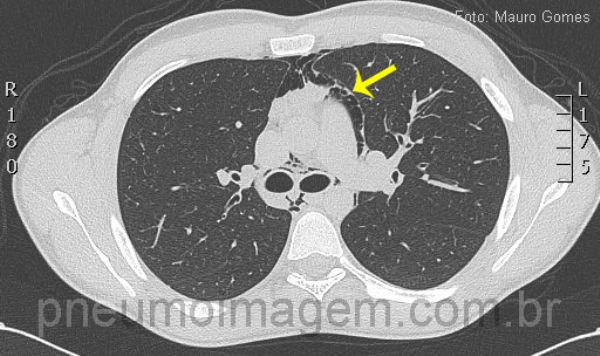

Corte tomográfico ao nível da carina demonstra a presença de ar dissecando as estruturas mediastinais, vasculares e brônquios. Observe a pleura deslocada da aorta devido à interposição de ar (seta). O pneumomediastino pode ocasionar dor torácica com irradiação para o pescoço, dispneia e enfisema subcutâneo, sendo uma rara complicação da asma.

CT slice at the level of the carina demonstrating the presence of air dissecting mediastinal, vascular and bronchial strucutures. Look at the pleura displaced of the aorta due to the interposition of air (arrow). Pneumomediastinum can cause chest pain irradiating to the neck, dyspnea and subcutaneous emphysema, being a rare complication of asthma.